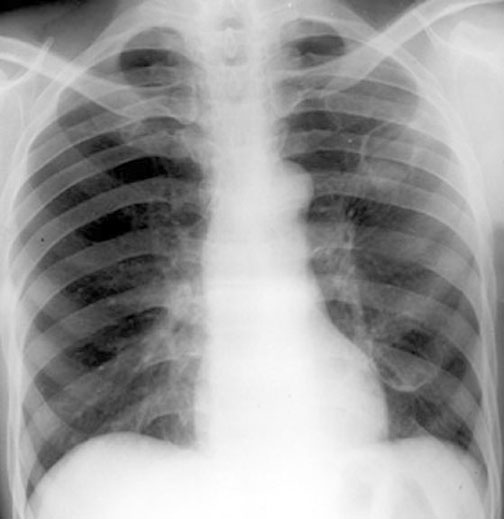

2 Thin Walled Cavities

Old Coccidioidomycosis